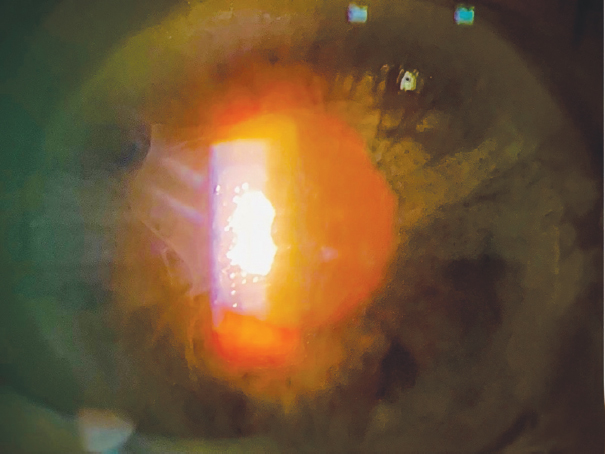

Послеоперационный фибриноидный синдром (ПФС) — термин, предложенный Э.В. Бойко, — является осложнением офтальмологических операций, в частности, факоэмульсификации, возникающим в раннем послеоперационном периоде и проявляющимся симптомокомплексом в виде отложения фибрина на поверхности интраокулярной линзы (ИОЛ) и радужки (рис. 1, 2) на фоне сохранённого рефлекса с глазного дна при отсутствующем или минимальном витреите по данным сонографического исследования стекловидной полости и имеющим непосредственную связь с выполненным хирургическим вмешательством [1–3]. Патогенез данного состояния до конца не изучен, считается, что в его основе лежит стерильное воспаление с нарушением проницаемости гематоофтальмического барьера, затрагивающее структуры, которые формируют переднюю камеру. В пользу асептической природы ПФС говорит его купирование без применения антибиотиков, а также крайне редкое возникновение гипопиона [4]. Однако возможной причиной данных изменений может быть и низковирулентная флора, не способная привести к возникновению эндофтальмита [5]. К факторам риска развития ПФС относят чрезмерную травматизацию радужной оболочки, способной выделять большое количество провоспалительных цитокинов (простагландинов) [6], например при выполнении экстракапсулярной экстракции катаракты [7], наличие псевдоэксфолиативного синдрома и сопутствующей ему слабости цинновых связок [8], неполное удаление хрусталиковых масс [1].

Рис. 1. Проявления послеоперационного фибриноидного синдрома: отложение фибрина на интраокулярной линзе и радужке c его распространением в радужно-роговичный угол

Fig. 1. Postoperative fibrinoid syndrome manifestations: fibrin depositions on the intraocular lens and iris surface spreading into the iridocorneal angle

Рис. 2. Сохраненный розовый рефлекс с глазного дна на фоне выпота фибрина

Fig. 2. Preserved red reflex from the funduspresence in the setting of fibrin exsudation ion